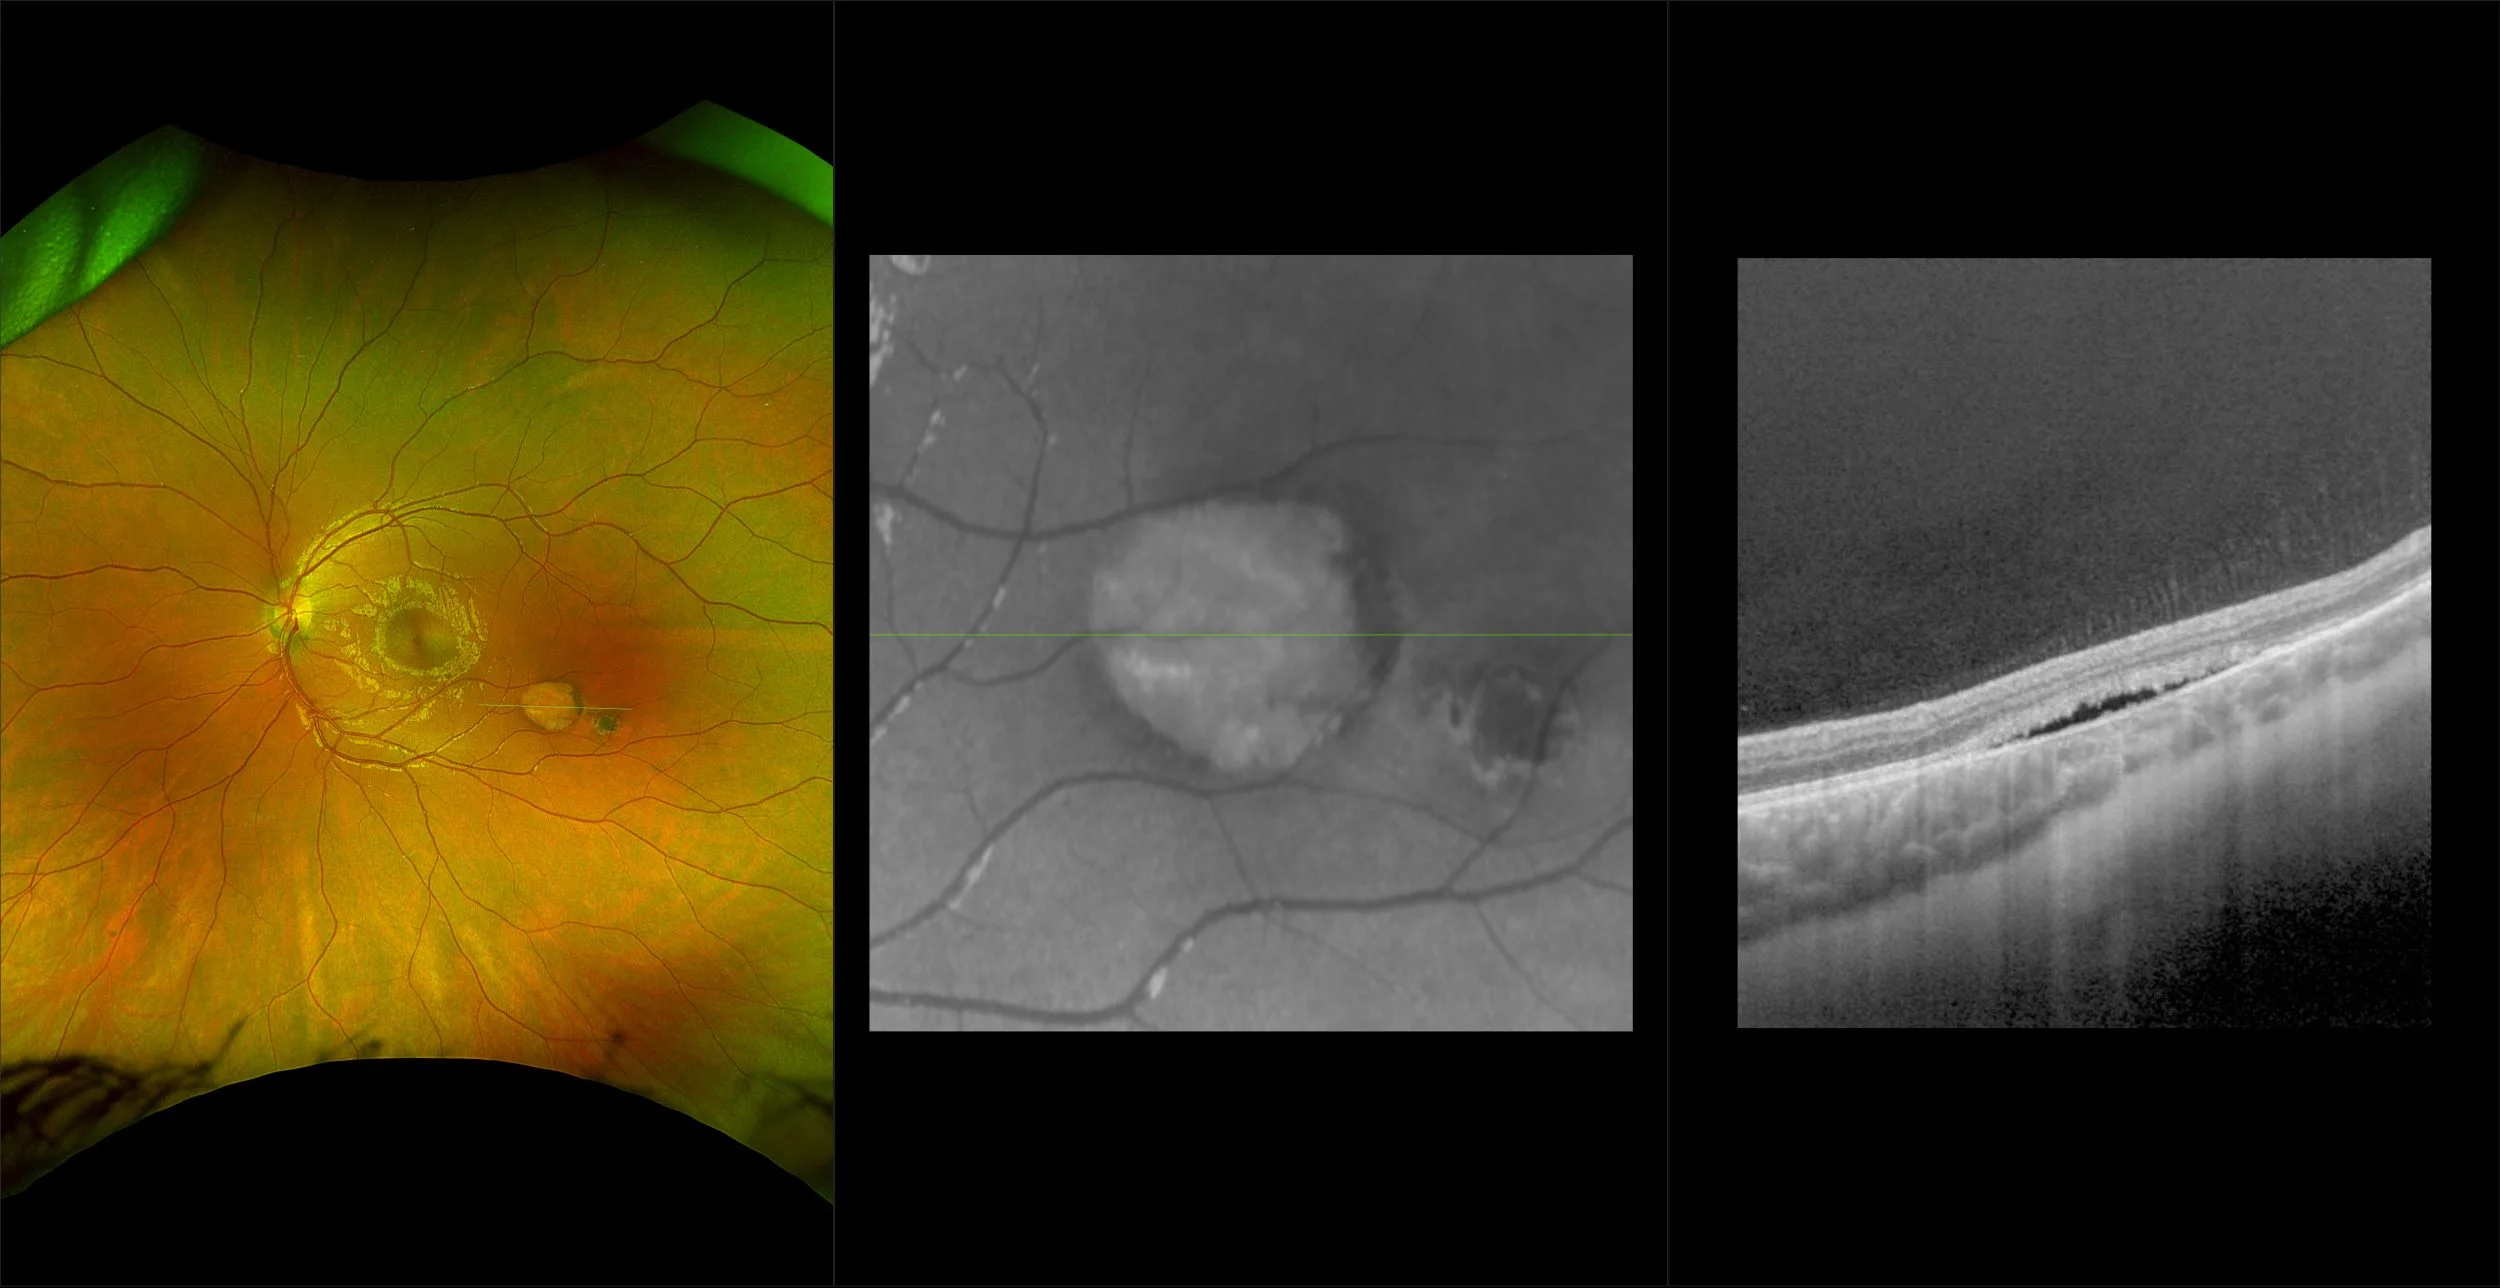

Congenital Hypertrophy of the Retinal Pigment Epithelium (CHRPE)

A thickening of the retinal pigment epithelium present at birth. The thickening appears on funduscopic examination as anoval, black, clearly demarcated lesion within which there are atrophic areas surrounded by a halo that has no pigment.